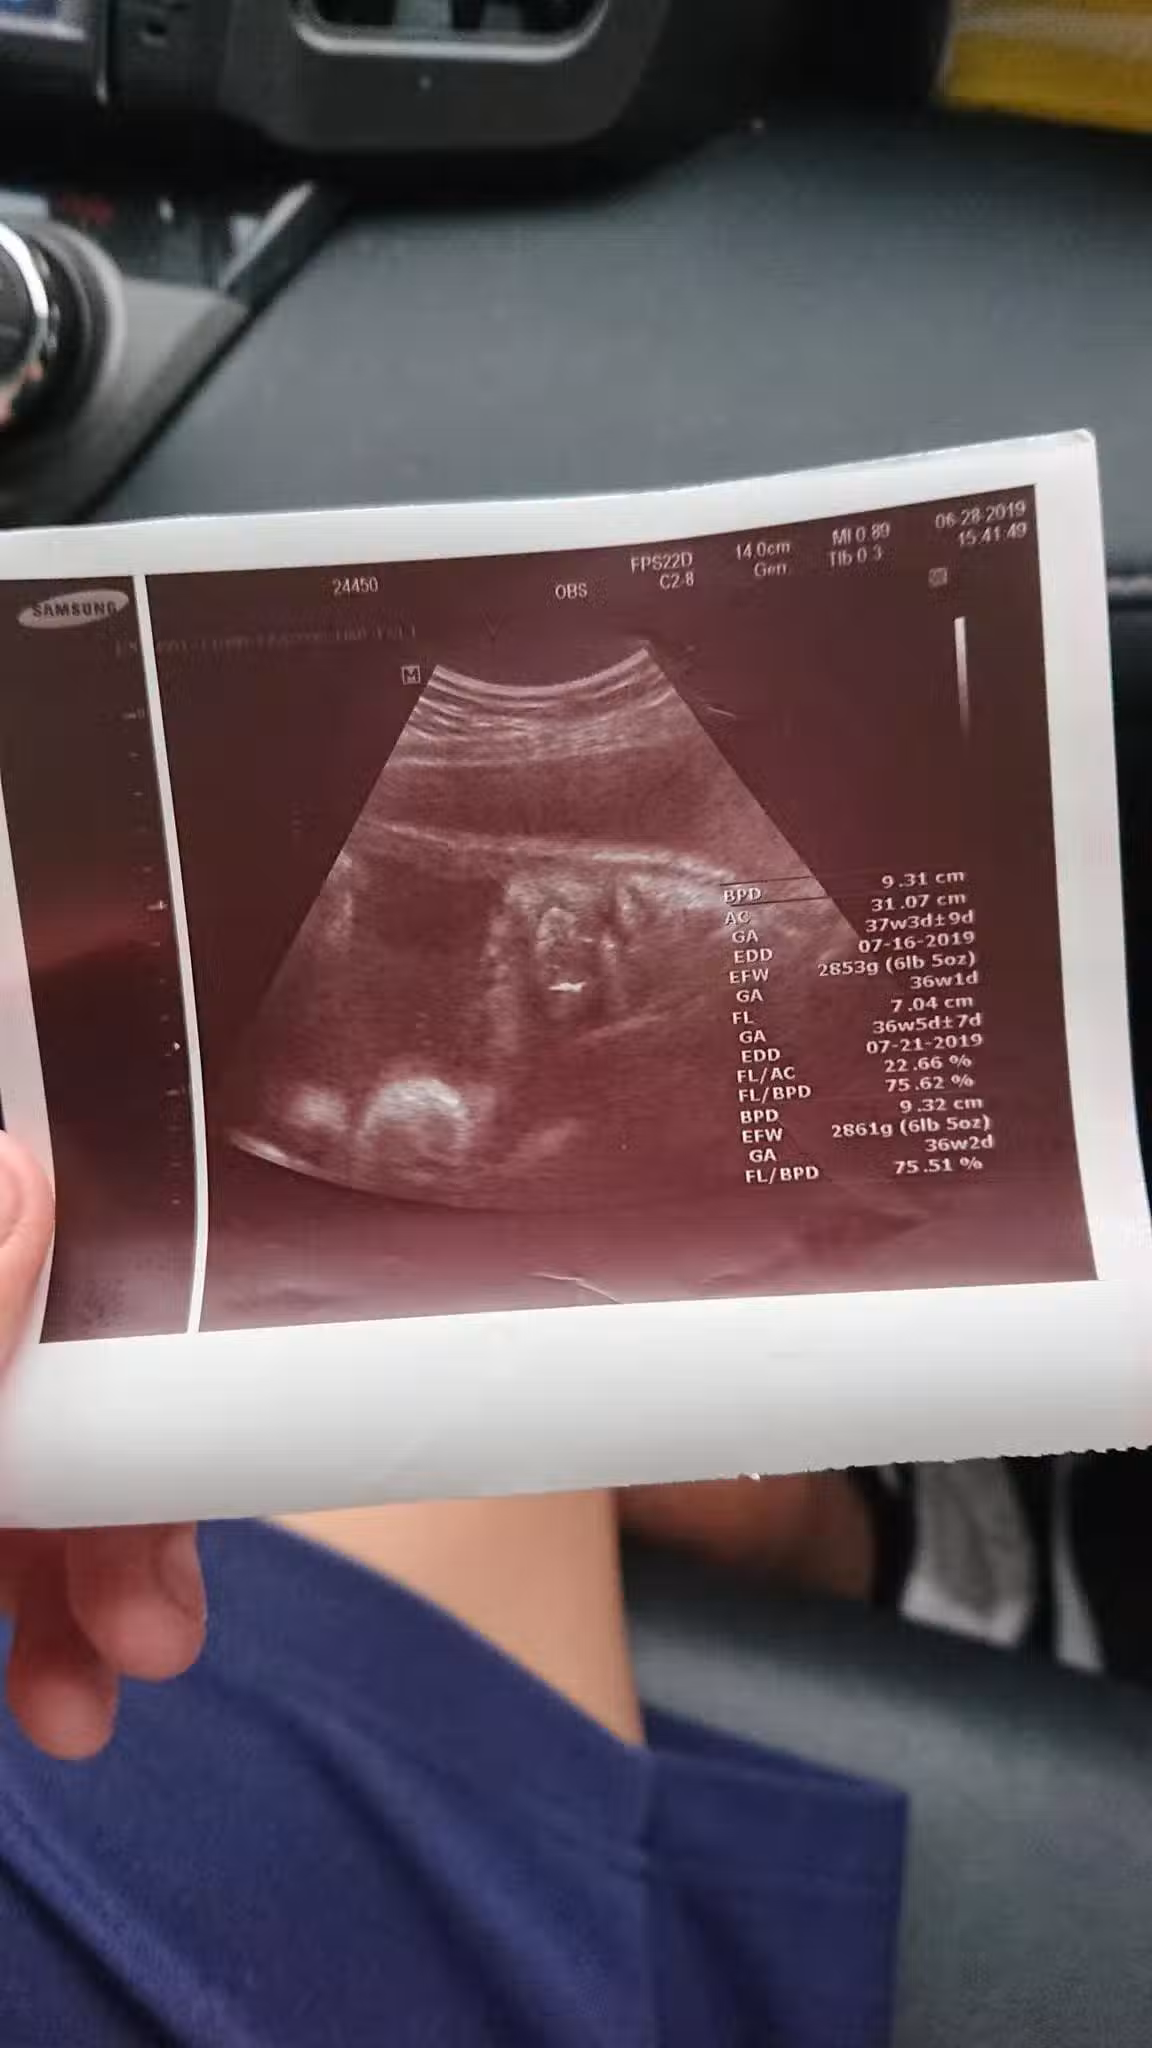

圖片來源:爆怨公社

沒想到兒子女友已經懷孕7個月了,當下他只覺得完蛋了,不知女方家長會怎麼處理,就先帶著高一兒子去見女方家長,還好女方家長很明理,認為事情發生了罵也沒用,就好好讓事情圓滿落幕,由於女方一直不敢告訴家人,所以也沒做產檢,去醫院檢查後,醫生說「胎兒是個男孩,已經約37週大,而且預產期大約在7月中」,所以孩子是一定要生下來的,7月1號時女方再度去醫院,竟然已經開了2指,然後7月2號早上小孩就出生了,原PO看到小孫子很開心也很激動,還自嘲說「在我42歲這年,我當上了阿公,我老婆38歲當了阿嬤,而我兒子竟然只給我們4天的時間心理準備……太刺激的禮物了。」。